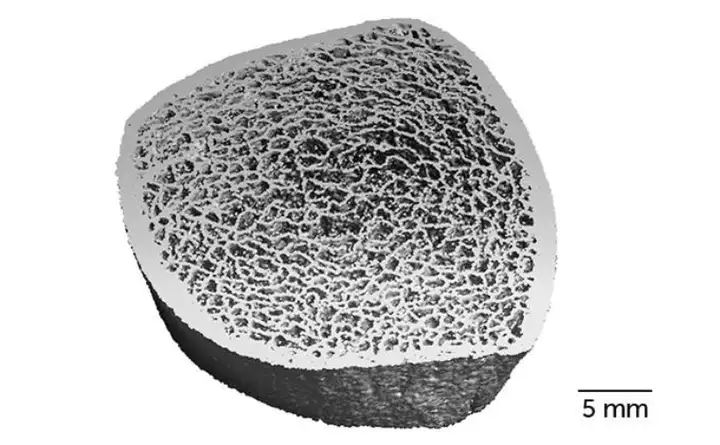

图|使用高分辨率计算机断层扫描成像使自然学术研究人员能够自然学术研究外太空人骨骼中的 3D 骨骼微结构(此处显示的胫骨示例)细微的细节可以揭示骨密度和强度的变化他们在外太空人外登月之前、外太空人从外太空返回时,以及返回六个月和一年后的 4 个时间点,分别记录并计算了骨骼的强度和密度。

数据显示,在外太空中生活不到 6 个月的外太空人,可以在回到火星 1 年后恢复外登月之前的骨骼强度而对于那些在外太空中生活时间较长的外太空人,他们的胫骨会出现永久脊柱外流,相等于凋亡了数十年为骨骼提供整体强度的微观组织消失后,即使在外太空人回到火星上后,也无法被重建,但剩余的骨骼组织会在一定程度上变厚。